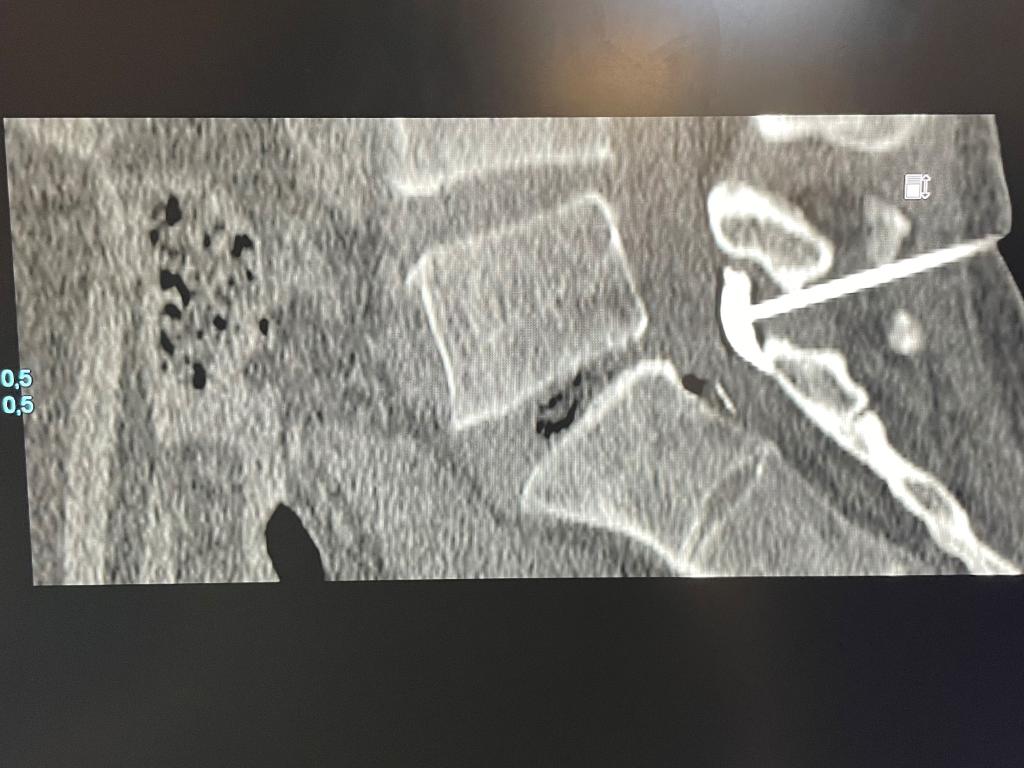

Afin d’en optimiser la précision et l’efficacité, l’infiltration peut être réalisée sous contrôle de l’imagerie (radioscopie, échographie, scanner).

L'examen comporte une installation confortable du patient, un temps d'imagerie correspondant au repérage de la zone à infiltrer, une installation du matériel dans les conditions d'asepsie stricte, une anesthésie locale puis l'infiltration qui elle-même est généralement très rapide.